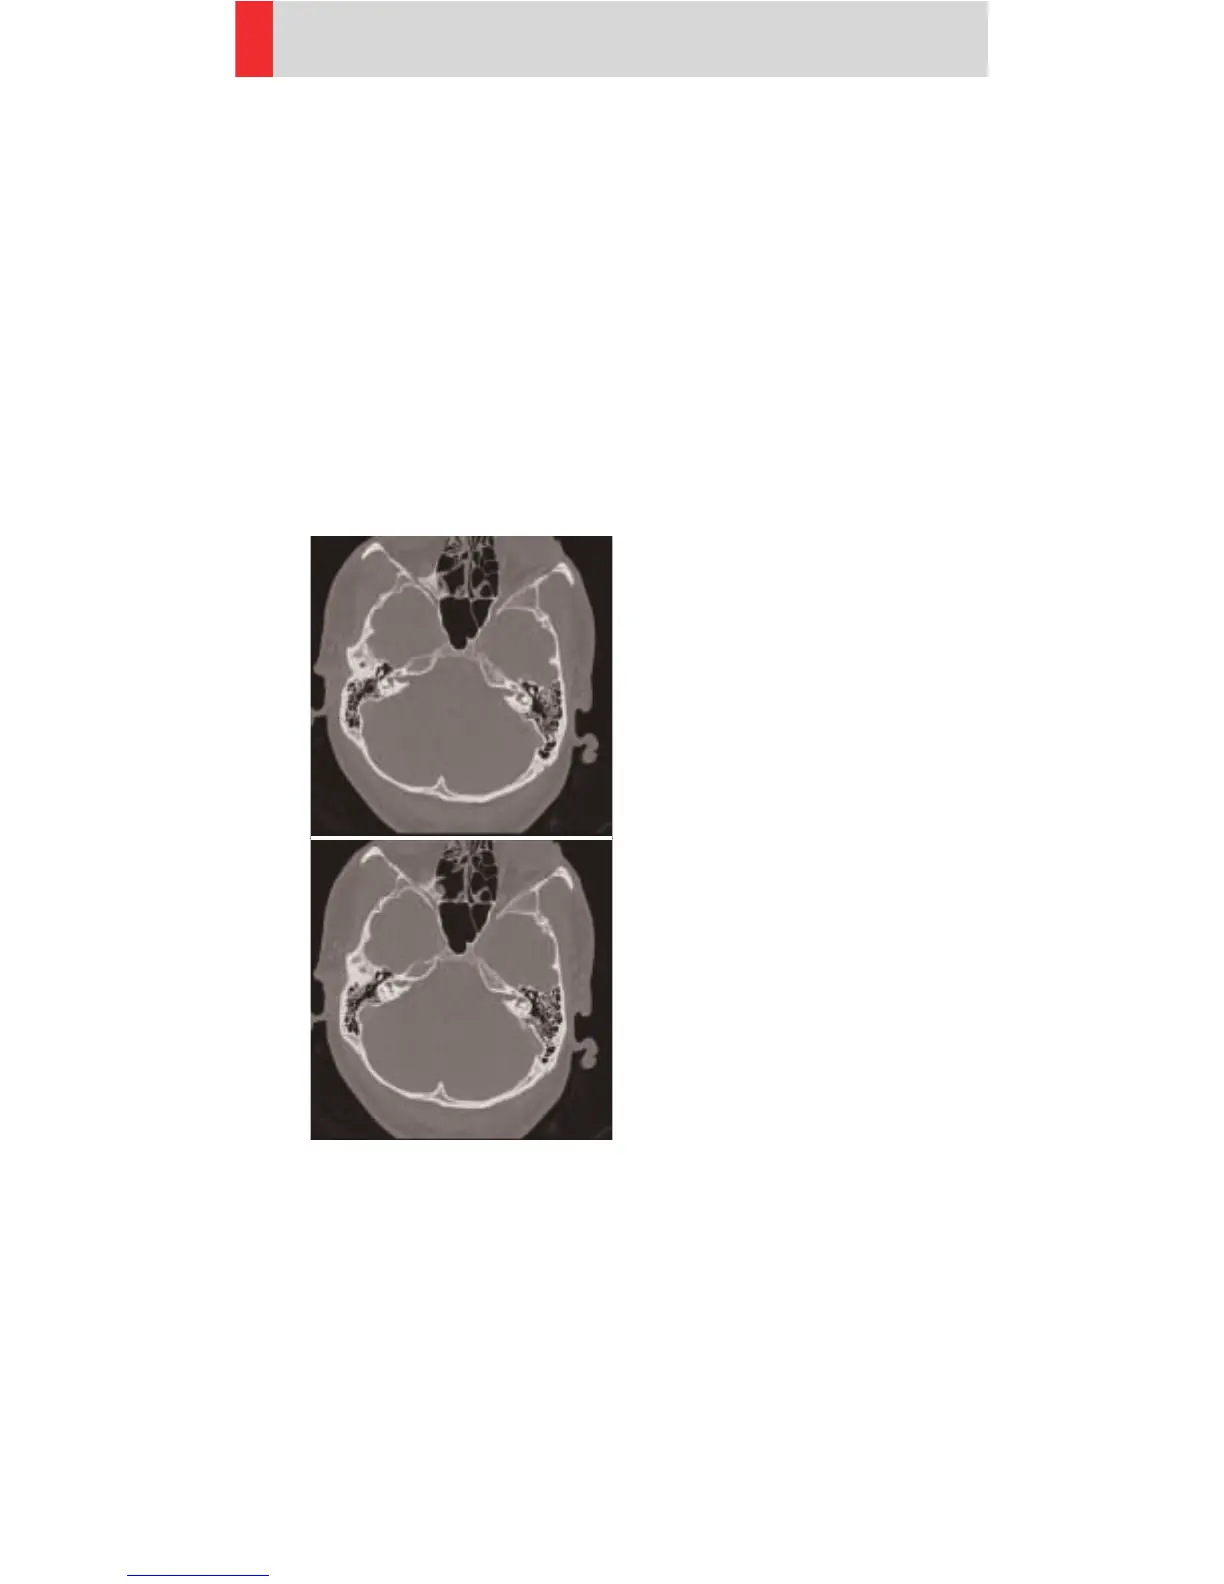

InnerEarSeq

Indications:

Sequence mode for inner ear High Resolution studies,

e. g. inflammatory changes, tumorous processes

of pyramids, cerebellopontine angle tumors, post-

traumatic changes, etc.

The scan length is 47 mm and a typical gantry tilt of

-20° is predefined.